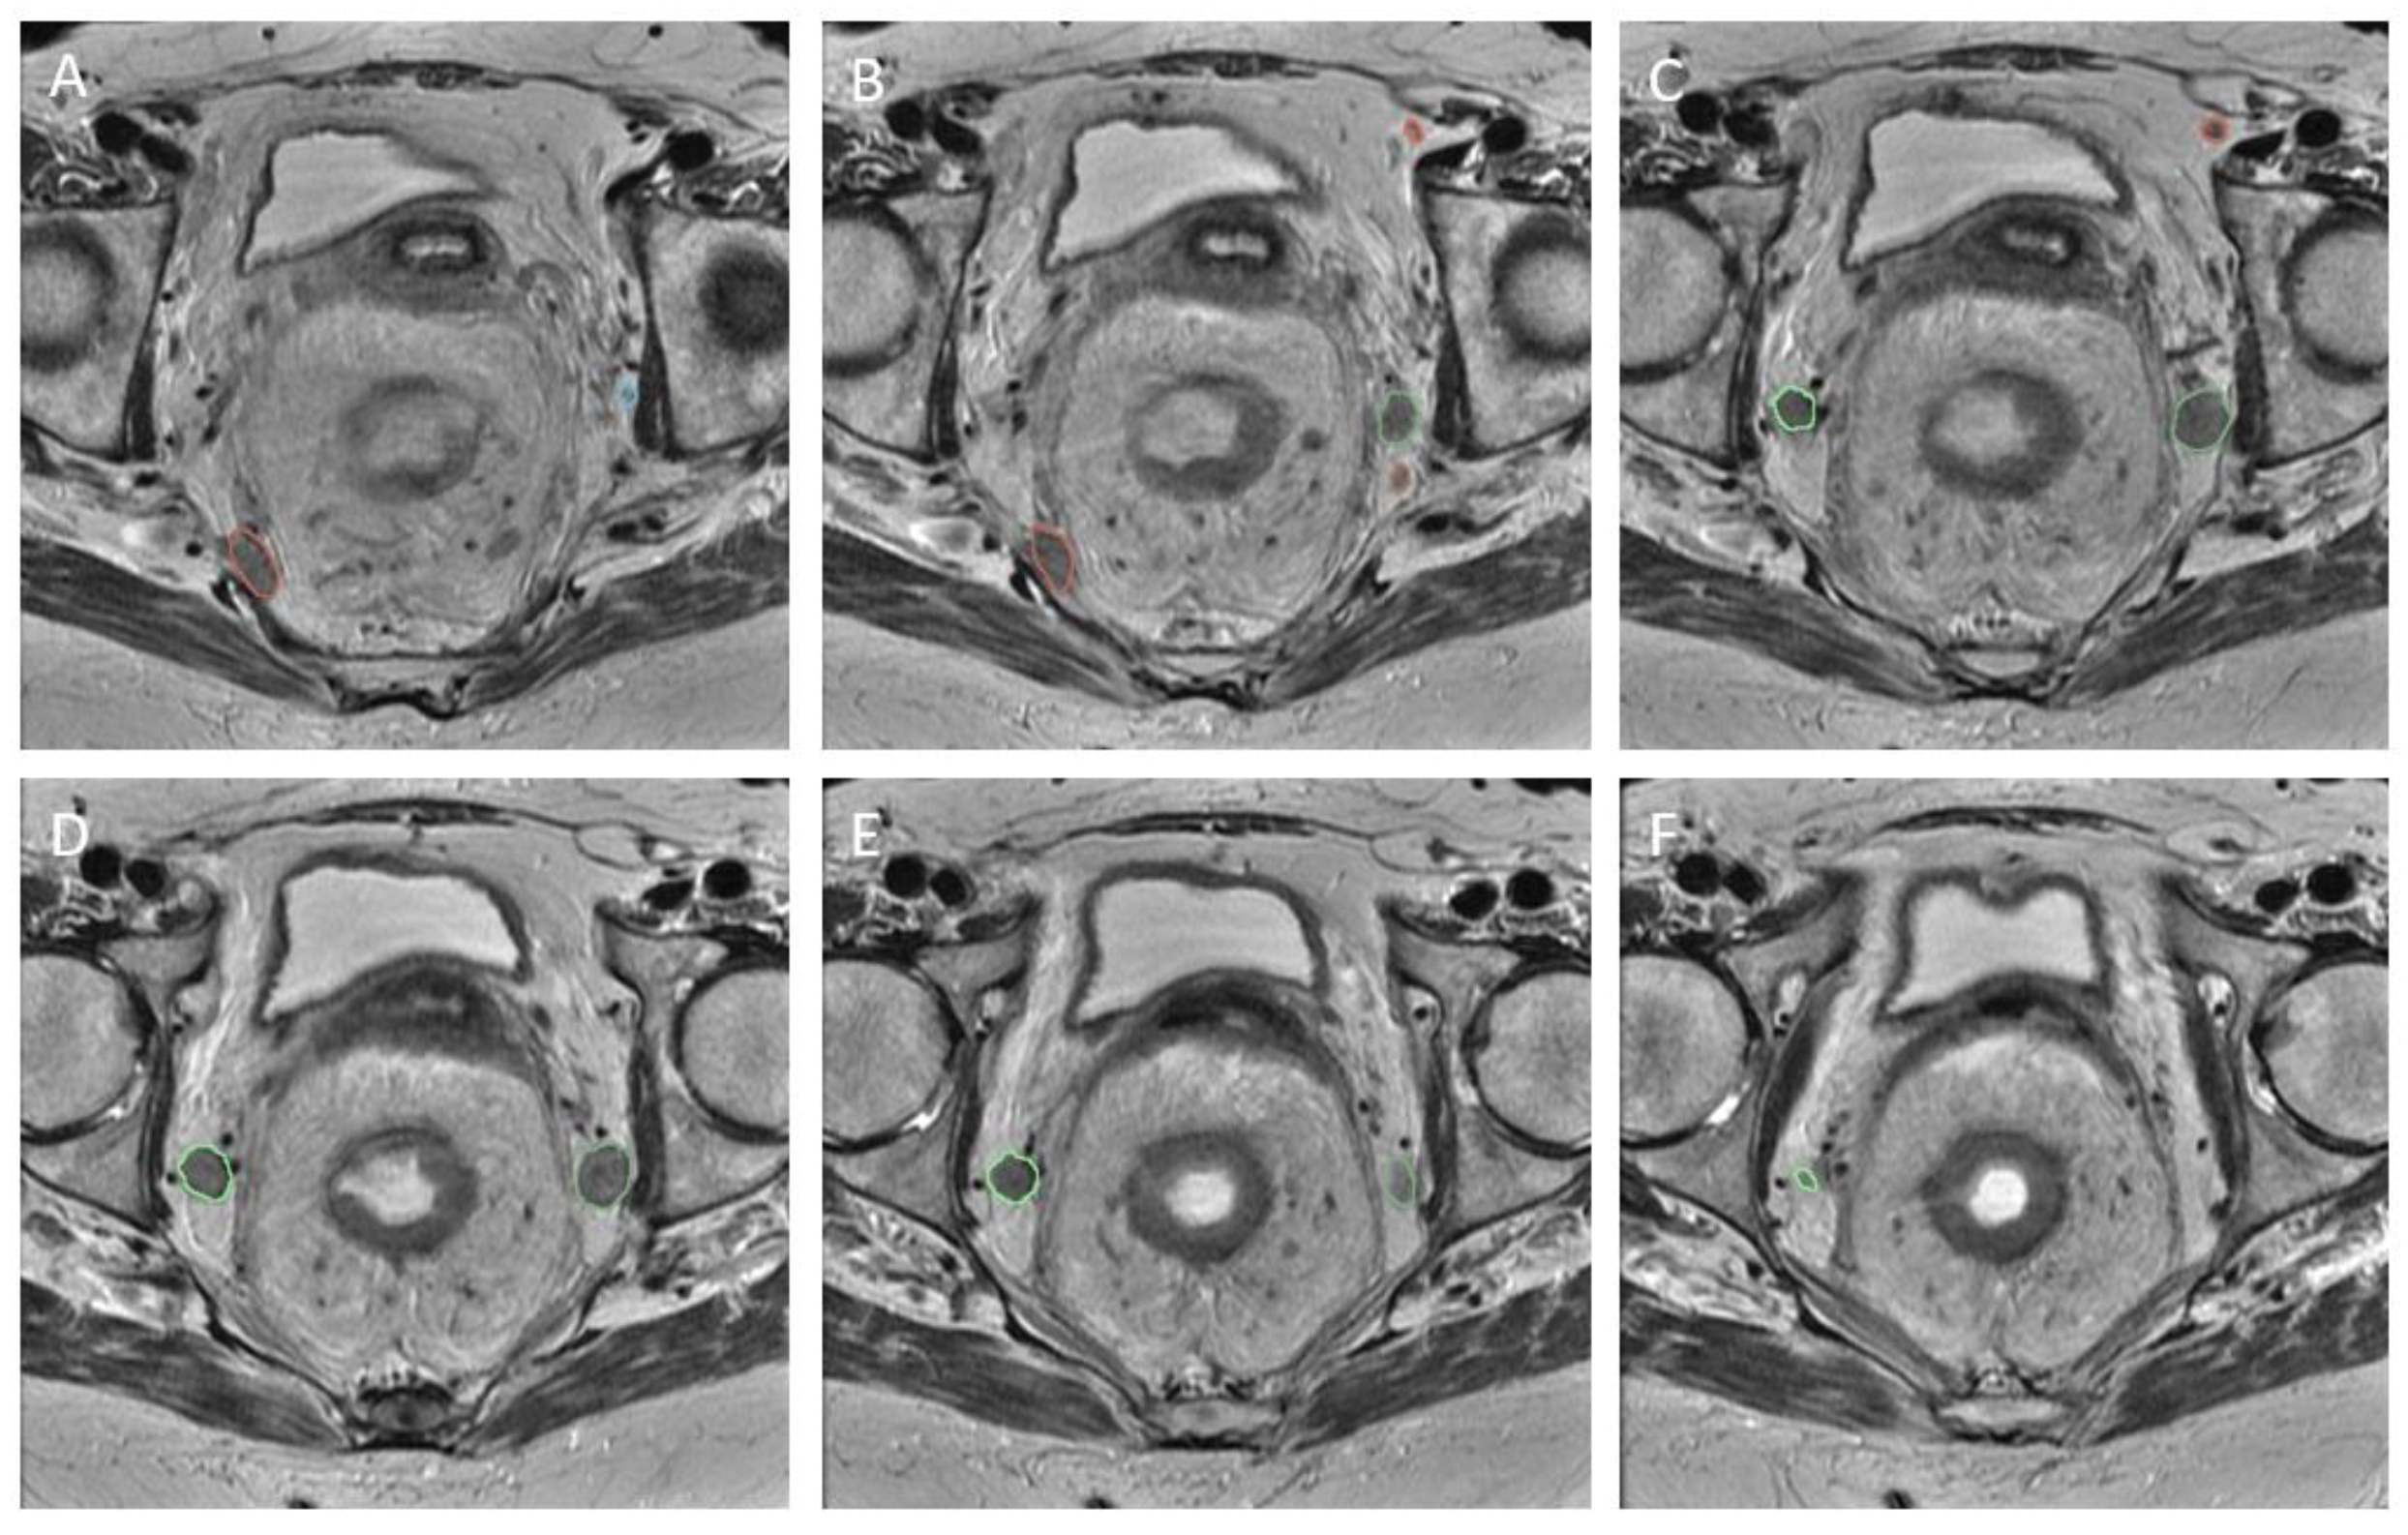

2.3. Image Segmentation